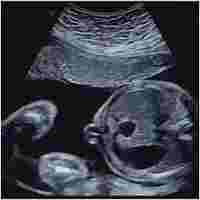

| Abstract | Abstract Background The implementation of genomic testing in pregnancy means that couples have access to more information about their child’s genetic make-up before birth than ever before. One of the resulting challenges is the management of genetic variations with unclear clinical significance. This population-based study will help to close this critical knowledge gap through a multidisciplinary cohort study of children with and without genomic copy number variants (CNVs) diagnosed before birth. By comparing children with prenatally-ascertained CNVs to children without a CNV, we aim to (1) examine their developmental, social-emotional and health status; (2) measure the impact of prenatal diagnosis of a CNV on maternal perceptions of child health, behavior and development; and (3) determine the proportion of prenatally-ascertained CNVs of unknown or uncertain significance that are reclassified as benign or pathogenic after 2 or more years. Methods This study will establish and follow up a cohort of mother-child pairs who have had a prenatal diagnosis with a chromosomal microarray from 2013-2019 in the Australian state of Victoria. Children aged 12 months to 7 years will be assessed using validated, age-appropriate measures. The primary outcome measures will be the Wechsler Preschool and Primary Scale of Intelligence IV (WPSSI-IV) IQ score (2.5 to 7 year old’s), the Ages and Stages Questionnaire (12-30 months old), and the Brief Infant- Toddler Social and Emotional Assessment (BITSEA) score. Clinical assessment by a pediatrician will also be performed. Secondary outcomes will be scores obtained from the: Vineland Adaptive Behavior Scale, Maternal Postnatal Attachment Questionnaire, the Vulnerable Child Scale, Profile of Mood States, Parent Sense of Competence Scale. A descriptive analysis of the reclassification rates of CNVs after ≥2 years will be performed. Discussion This study protocol describes the first Australian cohort study following children after prenatal diagnostic testing with chromosomal microarray. It will provide long-term outcomes of fetal genomic variants to guide evidence-based pre-and postnatal care. This, in turn, will inform future efforts to mitigate the negative consequences of conveying genomic uncertainty during pregnancy. Trial registration ACTRN12620000446965p ; Registered on April 6, 2020. |